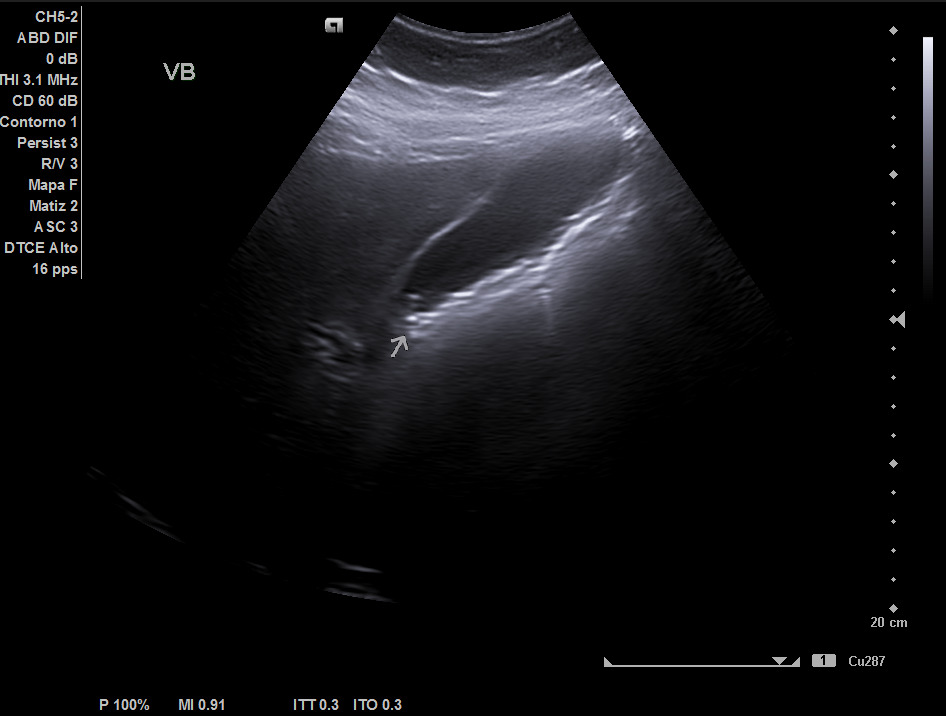

Hallazgos ecográficos

Hígado de tamaño, forma y ecoestructura conservadas, con parénquima homogéneo. Vena porta de calibre conservado. Colédoco dilatado, de 8,8 mm. Vesícula biliar de paredes gruesas y edematizadas (5,4 mm) en cara posterior, con contenido ecogénico y 2 microlitiasis en su infundíbulo.